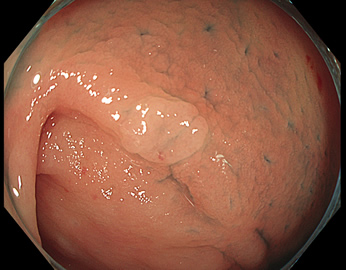

写真だけ、見ると「言われてみるとTXIの方が認識しやすい。でも僅かの差」と感じるでしょうが、この「僅かの差」が、人間の脳での検出には大きな差になります。青い色素(インジゴ・カルミン)が非常に強調され、粘膜の凸凹が明瞭になるのが特徴です。

通常観察 TXIモード

青い色素は追加していません![]()

特に、下のような「Ub型(全く凸凹の無い完全に平坦な病変)」は、以前は「ほとんど見つからなかった」のが、TXIを使うようになってから「日常的に」見つかるようになりました。